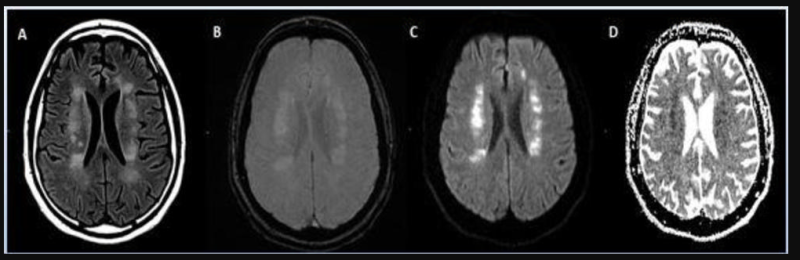

This photo gallery shows the variety of radiological presentations of COVID-19 (SARS-CoV-2) in medical imaging, including computed tomography (CT), radiograph X-rays, ultrasound, echocardiograms and magnetic resonance imaging (MRI). The radiology images show examples of typical COVID pneumonia in the lungs and the numerous complications the virus causes in the body in multiple organs, including the brain, kidneys, heart, abdomen and vascular system.